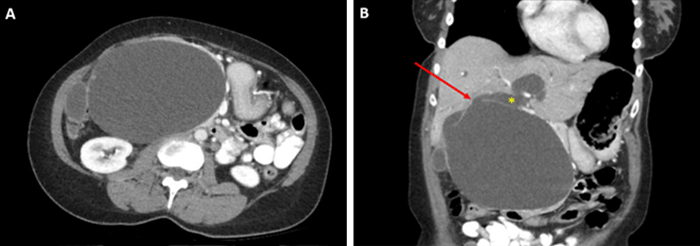

A 40-year-old previously healthy woman presented to her primary care physician with new fecal urgency, diffuse pruritis, and an abdominal mass. Physical examination was remarkable for jaundice, scleral icterus, and a palpable 10 cm right upper quadrant abdominal mass. Laboratory tests revealed a total bilirubin of 9.2, AST of 203, ALT of 174, and alkaline phosphatase of 380. An abdominal CT scan revealed significant cystic degeneration of the common bile duct suspicious for a type I choledochal cyst (Figure 1).

Figure 1. CT Scan Obtained at Time of Presentation. Published with Permission

A) Large cyst with some intramural nodularity; B) coronal view of cyst with associated intrahepatic biliary dilatation. Arrow demonstrates area where common bile duct (*) was kinked at inlet to large cyst, causing obstruction

The cyst's large size resulted in kinking of the normal-caliber proximal common bile duct and moderate dilation of the intrahepatic biliary tree. Given the available CT was high quality and adequately delineated the biliary anatomy, we did not feel additional imaging, including MRCP, was necessary. Due to the patient's biliary obstructive symptoms, concern for progression to cholangitis, and potential for malignant transformation of the cyst wall, the patient was offered an extrahepatic bile duct resection with biliary-enteric reconstruction.